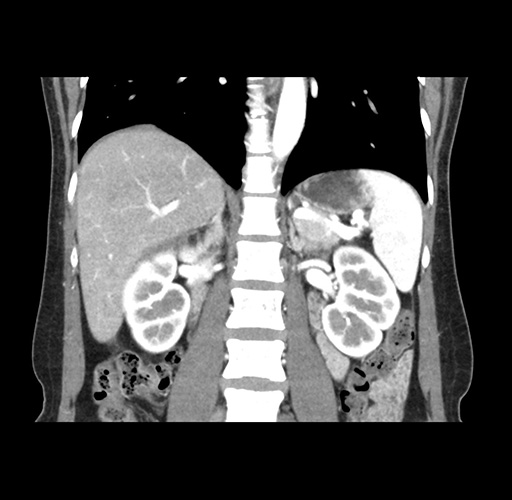

Left lateral sectionectomy [case 12]

Imaging Analysis

Look through the patient's CT scan to identify any areas of concern for the necessary procedure.

Based on your CT findings, which issue(s) would give reason for "planned slowing down moment(s)" in this case?

Considering a standard left lateral sectionectomy procedure, what step(s) of the operation would you do differently in this case ?